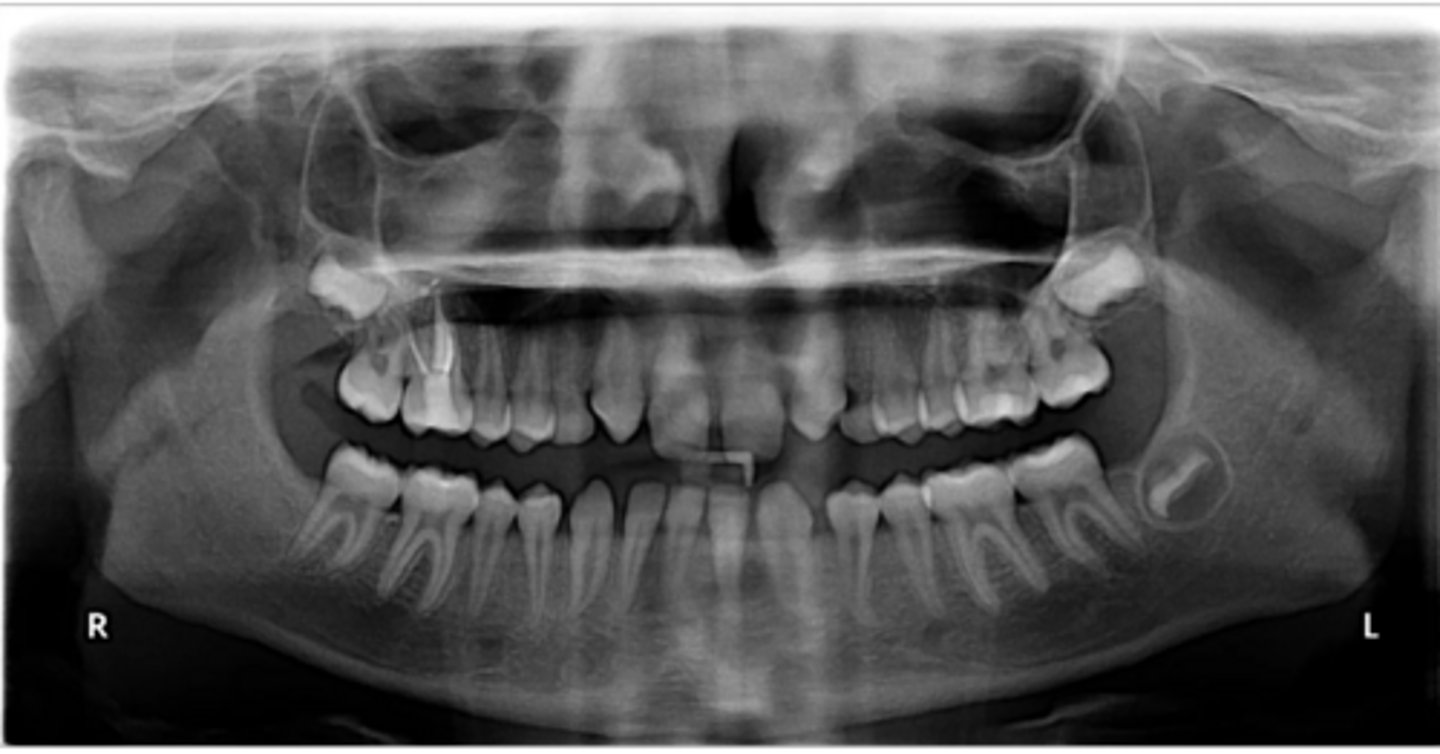

Right primary canine

Are there retained primary teeth?

Yes

Are there any impacted teeth?

Are the condyles symmetrical?

Is there a dilacerated root?

No

The mandibular left side has normal premolar/canine eruption, but the rigth side is abnormal.

Is the eruption pattern of this patient normal or not?

Are there any supernumerary teeth?

Are there any retained primary teeth?

Not at this stage

Are there impacted teeth?

Yes, within the range of normal

Symmetric condyles?

Yes - maxillary first molar

Dilacerated roots?

Yes - laterals

Are there congentially missing teeth in the maxillary arch?

Yes - an incisor

Are there congenitally missing teeth in the mandibular arch?

Yes - upper right near the premolar

Any impacted teeth?

Can't see, so can't say

Yes - #2, also #27?